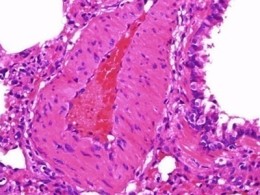

动脉粥样硬化...